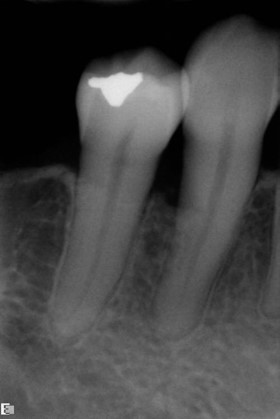

Fig 11. The success and efficacy of this approach was confirmed radiographically at 8 years post-treatment, as demonstrated by the stable gingival margins, thickened biotype with a connective tissue graft, and stable bone levels observed at the first thread of the fixture.

Figure 11

At 8 years post-treatment, implant bone levels were maintained as evidenced radiographically (Figure 11), with stable gingival margins and bone levels at the first thread of the fixture. There was minimal visible damage and scar tissue from the surgical approach to implant placement and tissue grafting to thicken the biotype. Despite the potential challenges, the use of growth factor technology and minimally invasive surgical techniques allowed the esthetic treatment goals for this case to be achieved for the long term (Figure 12).